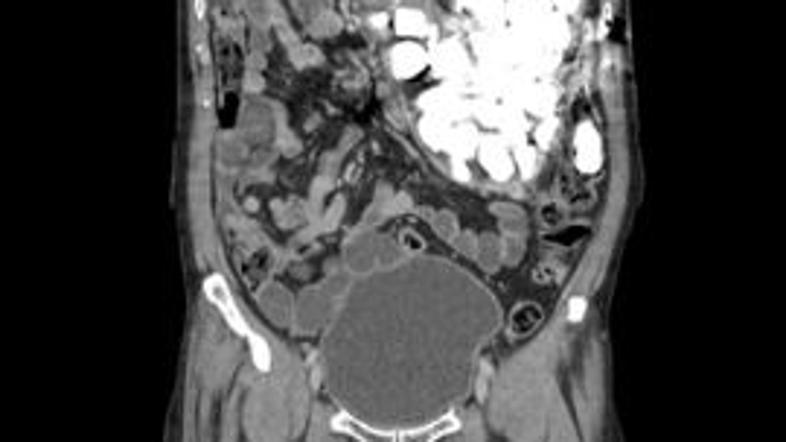

CT želodca

Računalniška tomografija (CT)  trebušnih organov je pokazala, da je bolnikov želodec napolnjen s tujki, po pogovoru pa je Južnokorejec priznal, da je pogosto zaužil kovance in kamenčke. To je počel, ko je bil zaskrbljen, saj ga je takšno početje pomirilo.